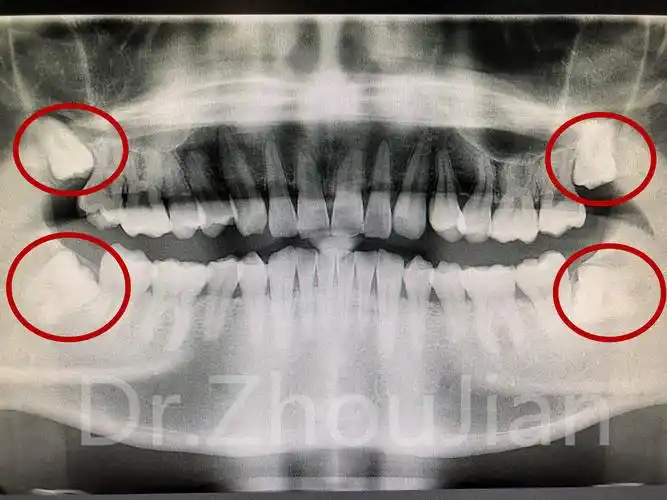

智齿生长的位置

两边智齿阻生齿的图片

位置不正的智齿

奇葩智齿大揭秘

【图】阻生智齿危害:引起周围软组织疾病